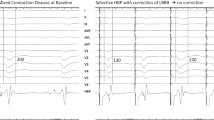

The raw data was analysed with ecSYNC software (CardioInsight Technologies Inc., Cleveland, OH) in order to derive 4 key activation metrics: VVtat (global biventricular total activation time); VVsync (global left/right ventricular electrical synchrony); LVtat (left ventricular total activation time); LVdisp (global left ventricular dispersion of activation) (see supplementary material for further information). The activation wave front angle was assessed from a screenshot of the isochrone maps for intrinsic and RVP with the cardiac shell orientated in a left anterior oblique cranial view where the basal to apical distance was maximal. The wave front angle was measured using an on-screen protractor application over each activation map screenshot (Protractor version 10.0, Softlibs) (Fig. 1). The angle measured was a user-selected most prominent isochrone line on each individual; as the cardiac geometry for the intrinsic and RVP activation maps are identically aligned, each patient’s LBBB map generates a reference wave front angle for RV pacing; the same isochrone was selected when comparing between intrinsic and RVP. The investigator was blinded for which patient and whether paced or intrinsic for each pair of maps. In order to define the final American Heart Association segments (16 segment model) to be activated, these final segments had to contain the latest isochrone on the activation map; in total, 30 isochrones were present on each map. For each patient on the intrinsic and the RVP map, there can be more than one segment which contains the final isochrone.

Screenshot of calculation of wave front angle. On-screen protractor (Protractor Version 10.0, Softlibs) superimposed on the activation map. The predominant wave front angle is then measured (pink dashed lines); the angle of the same isochrones is then directly compared between the right ventricular pacing map and the LBBB map as both activation maps are identically aligned

When comparing activation time parameters between intrinsic (LBBB) and RVP, there was a significant increase in LVtat and LVdisp with RVP (87.4 ± 21.1 ms vs. 102.8 ± 19.6 ms, p = 0.046 and 27.6 ± 6.9 ms vs. 33.4 ± 5.9 ms, p = 0.025 respectively); there was no significant change in VVtat but a significant reduction in VVsync (45.1 ± 20.2 ms vs. 35.9 ± 17.1 ms, p = 0.01). The reduction in VVsync and increase in LVdisp were also present in the apical group analysis (38.2 ± 14.5 ms vs. 27.8 ± 11.3 ms, p = 0.035 and 25.7 ± 6.0 vs. 33.3 ± 6.9 ms, p = 0.046 respectively), with no statistical change in VVtat or LVtat. However, analysing the data for the septal pacing group demonstrated no difference between LBBB and pacing for any activation parameters. The activation wave front angle rotated anticlockwise from LBBB with RVP (82.5 ± 25.2o vs. 62.1 ± 31.7o, p = 0.026) and RVAP (76.7 ± 28.9o vs. 50.0 ± 27.6o, p = 0.049) with no significant change with RVSP (93.0 ± 13.5o vs. 84.0 ± 28.4o, p = 0.548) (Table 2, Figs. 2 and 3).

Box and whisker plots for activation times and wave front angles for intrinsic left bundle branch block (LBBB) and right ventricular pacing (RVP). VVsync—right/left ventricular electrical synchrony, VVtat—biventricular total activation time, LVtat—left ventricular total activation time, LVdisp—left ventricular dispersion of activation, WFA—wave front angle

Individual changes in activation times and wave from angles. The black dots represent right ventricular apical pacing and the red squares represent right ventricular septal pacing. Abbreviations as per Fig. 2